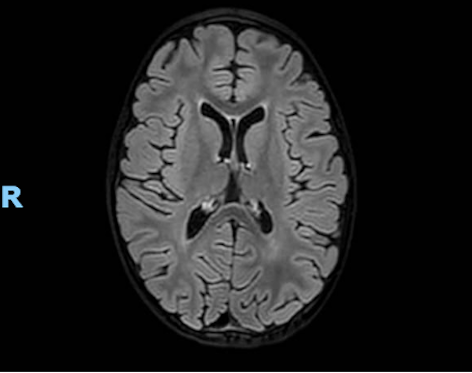

Per il quadro neurologico si richiede RM che evidenzia quadro di leucoencefalopatia con ipotrofia cerebrale (Figura 2). Dall’approfondimento anamnestico emerge che la bambina segue una dieta vegana e non ha mai eseguito integrazione vitaminica, dato confermato dal sopraggiunto valore di vitamina B12 (100 pg/ml, VN 191-663 pg/ml).